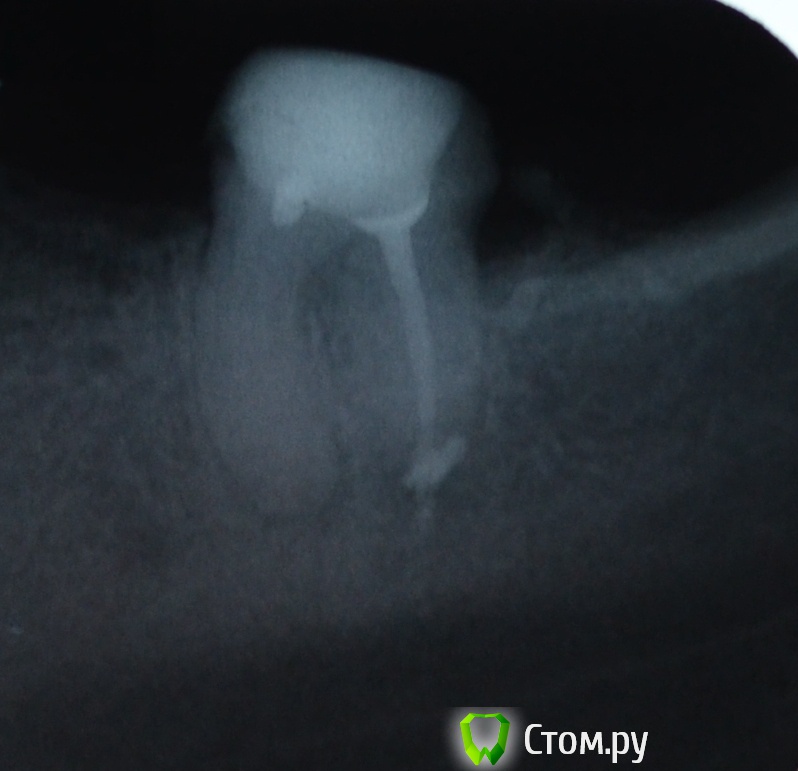

Zubilka Опубликовано 14 мая, 2014 Поделиться Опубликовано 14 мая, 2014 Приветствую! Навалилась проблема в виде двух нижних семерок. Точнее того, что от них осталось. Есть необходимость попытаться их спасти, ибо с обеих сторон необходимо протезирование по поричине отсутствия 5,6,8 зубов. Каналы попытались пролечить, но по ходу действия выяснилось, что они непроходимы. Посоветовали или так наляпать коронки на удачу, или удалить и копить на имплантацию. Собственно вопрос: стоит ли попытаться их лечить, или все на самом деле печально? Буду очень признательна за советы. Ссылка на комментарий

IvanK Опубликовано 14 мая, 2014 Поделиться Опубликовано 14 мая, 2014 Здравствуйте,тот, что на правом снимке, я бы удалил точно. есть у Вас панорамный снимок (ОПТГ)? какой вариант протезирования планируется? Ссылка на комментарий

red_butler Опубликовано 14 мая, 2014 Поделиться Опубликовано 14 мая, 2014 Согласен с Иваном, зуб на правом снимке удалять. Тот что на левом можно перелечить - ищите стоматолога-эндодонтиста, работающего с микроскопом. Но будьте готовы к тому, что качественное лечение с последующим протезированием, в финансовом плане может быть сопоставимо с имплантацией Ссылка на комментарий

Zubilka Опубликовано 14 мая, 2014 Автор Поделиться Опубликовано 14 мая, 2014 Спасибо за ответы. Подтвердили мои самые страшние опасения. Снимок пока только такой. А что вообще с правым не так? По какой причине необходимо удаление? Хочется понять. Он в таком состоянии простоял у меня почти 10 лет под коронкой, даже ни разу не тревожил. Если бы не решила заменить коронки на новые, кажется, еще бы простоял пару годков. Ссылка на комментарий

anvladd Опубликовано 14 мая, 2014 Поделиться Опубликовано 14 мая, 2014 (изменено) Лучше бы и левый убрать,бифуркация слабовата, не выдержит нагрузки,да и дорого будет, ставьте имплант. Изменено 14 мая, 2014 пользователем anvladd Ссылка на комментарий